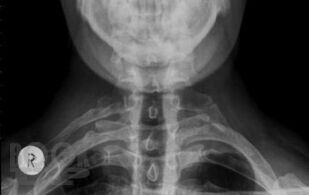

В учебном пособии, обобщающем многолетний педагогический опыт профессорско-преподавательского состава кафедры нервных болезней Военно-медицинской академии им. С. М. Кирова, с учетом данных современной литературы представлены сведения об анатомии, физиологии, заболеваниях и травмах спинного мозга. Отдельно рассмотрены вопросы эмбриогенеза, регенерации и аномалий развития спинного мозга. Пристальное внимание уделено топической диагностике спинальных поражений при сосудистых, инфекционных, демиелинизирующих, нейродегенеративных и системных заболеваниях. Специальные главы посвящены повреждениям спинного мозга при травмах, опухолях, воздействии экстремальных факторов, радиации и интоксикациях, а также современным методам исследования спинальной патологии и ее реабилитации. Издание иллюстрировано таблицами, схемами, рисунками и фотографиями, что облегчает восприятие и улучшает запоминание материала.